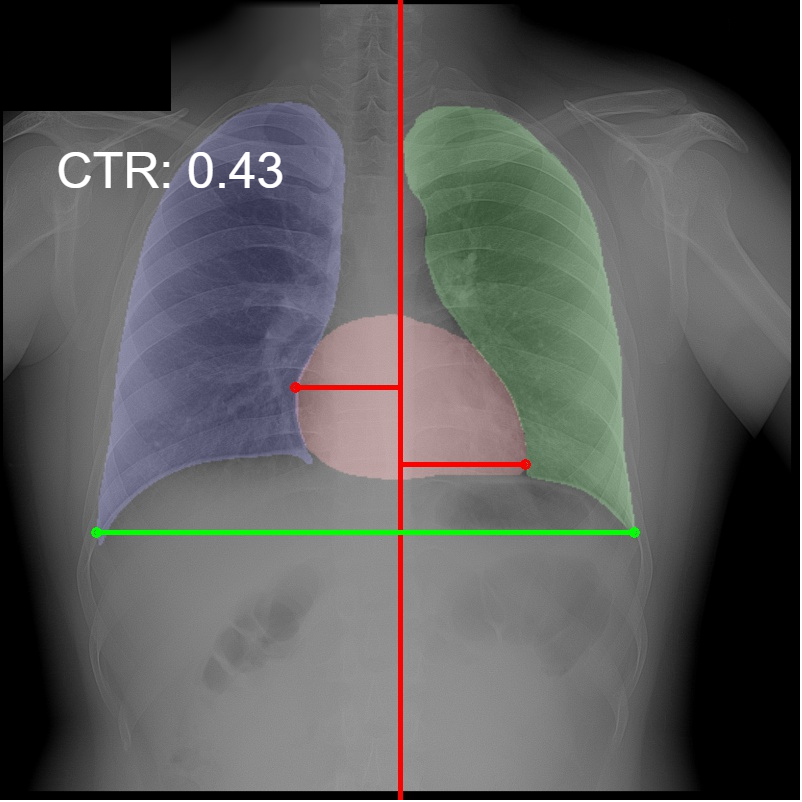

3.5 Cardiothoracic Ratio Calculation

After obtaining the masks, we calculate CTR with equation 1. We calculate cardiac diameter, , by finding the extreme points on the x-axis of the heart mask and calculate their x-axis distance. Thoracic diameter, , is calculated from extreme points from the lung mask. Figure 4 demonstrates the calculation of each component.

After obtaining heart and lung segments, we calculated , , and and marked them on the image along with CTR value calculated from Equation 1.

Figure 6 shows examples of our CTR calculation, where CTR values along with their , and measurement points are correctly identified. In this image, cardiomegaly is correctly detected by CTR value of .